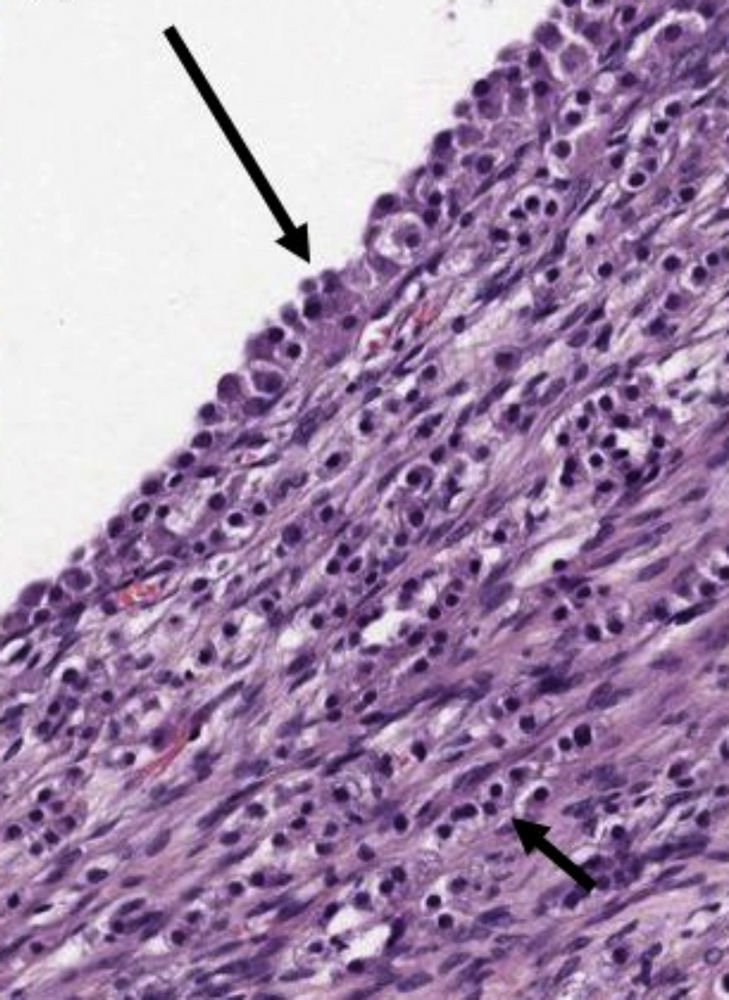

Se practica una laparoscopia diagnóstica para la toma de biopsia, objetivando la presencia de pelvis congelada y una masa abdominal. Se toma biopsia de la misma, siendo compatible con metástasis de carcinoma lobulillar de mama (fig. 7) Inmunohistoquímica: CK-19 (+ 100%), receptores de estrógenos (+ 90%), receptores de progesterona (–), Ki 67 (< 5% +), P53 (–) y Cerb-B2 negativo (0/+++).

Imagen histológica de la masa biopsiada. a) Tejido ovárico infiltrado, en la zona superior de la imagen, por las células tumorales, de pequeño tamaño y muy homogéneas entre sí. Abajo se aprecia parte de un cuerpo albicans (estrella). b) Infiltración del tejido adiposo epiploico por las células neoplásicas, algunas de ellas con morfología en «anillo de sello» (flecha). En el recuadro se aprecia positividad para citoqueratina 19 (CK19).

Desde el punto de vista histológico, en el carcinoma lobulillar, es característica la presencia de hileras de células tumorales, formando una «fila india», dispersas en la matriz fibrosa, así como células con grandes vacuolas citoplasmáticas, que recuerdan a las células en anillo de sello del carcinoma difuso gástrico, apendicular o colónico.